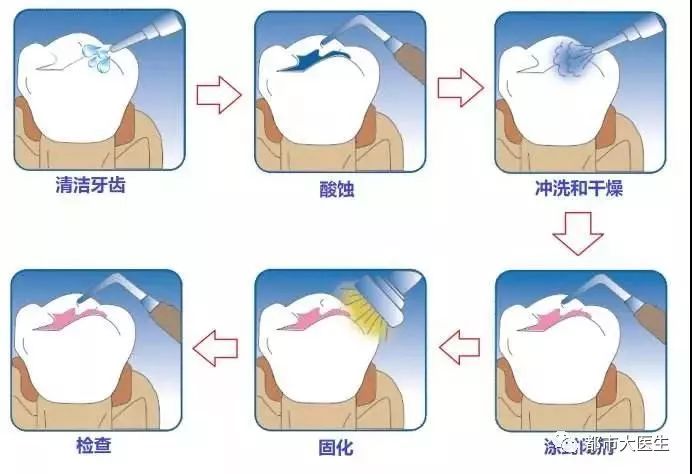

- 别等孩子的恒牙都烂完了,才知道这个预防蛀牙的好办法

- 蛀牙是需要及时补牙的,龋齿没能及时治疗,龋洞会越来越深,影响恒牙的